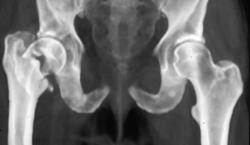

Stress Fracture Sacrum